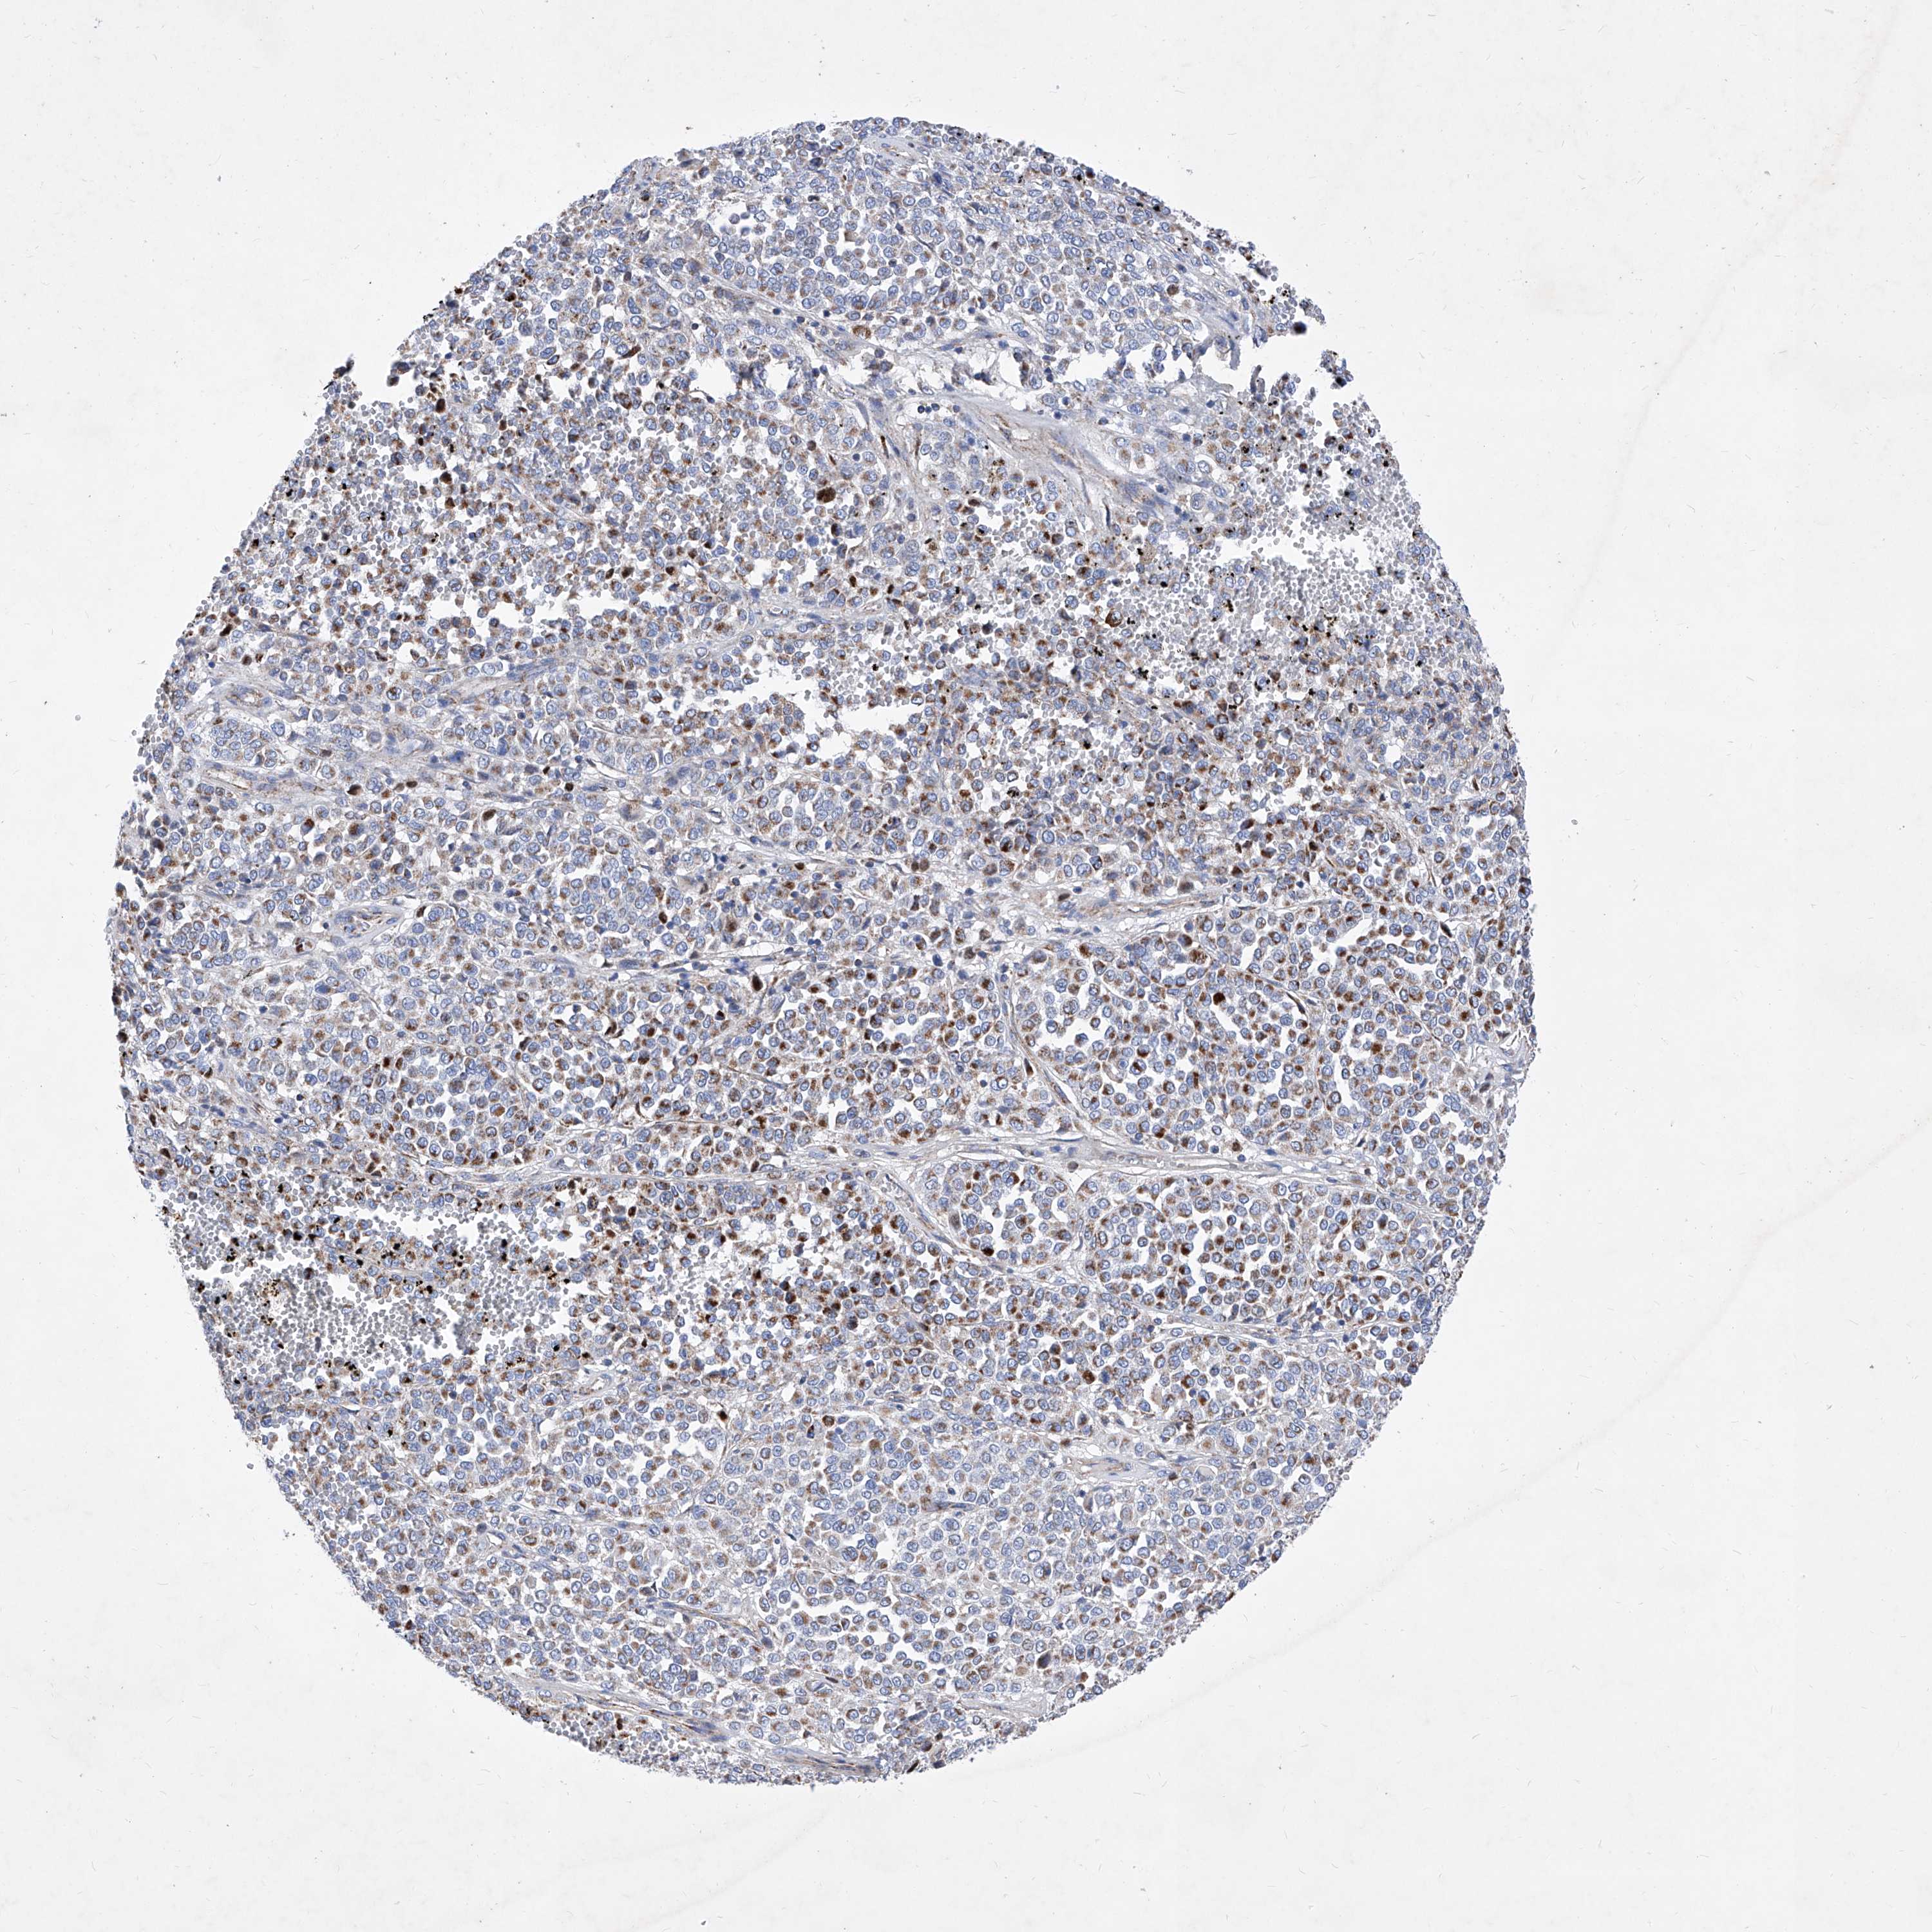

MELANOMA - Protein expressioni

A mouse-over function shows sample information and annotation data. Click on an image to view it in a full screen mode. Samples can be filtered based on level of antibody staining by selecting one or several of the following categories: high, medium, low and not detected. The assay and annotation is described here.

Note that samples used for immunohistochemistry by the Human Protein Atlas do not correspond to samples in the TCGA dataset.

Antibody stainingi

Antibody staining in the annotated cell types in the current human tissue is reported as not detected, low, medium, or high, based on conventional immunohistochemistry profiling in selected tissues. This score is based on the combination of the staining intensity and fraction of stained cells.

Each image is clickable and will lead to virtual microscopy that enables deeper exploration of all samples and also displays staining intensity scores, fraction scores and subcellular localization as well as patient and tissue information for each sample.

Antibody HPA031469

Staining

High

Medium

Low

Not detected

Intensity

Strong

Moderate

Weak

Negative

Quantity

>75%

75%-25%

<25%

None

Location

Nuclear

Cytoplasmic/membranous

Cytoplasmic/membranous,nuclear

Malignant melanoma, NOS

Malignant melanoma, Metastatic site